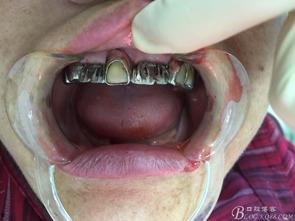

固定假牙的优点是稳定性好,不易脱落,使用寿命长。它通常由金属支架和陶瓷牙冠组成,既美观又耐用。不过,固定假牙的安装过程较为复杂,需要多次复诊。